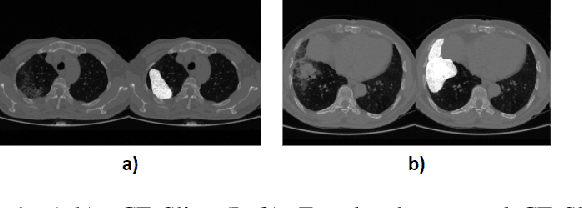

Abstract:Image segmentation plays a pivotal role in several medical-imaging applications by assisting the segmentation of the regions of interest. Deep learning-based approaches have been widely adopted for semantic segmentation of medical data. In recent years, in addition to 2D deep learning architectures, 3D architectures have been employed as the predictive algorithms for 3D medical image data. In this paper, we propose a 3D stack-based deep learning technique for segmenting manifestations of consolidation and ground-glass opacities in 3D Computed Tomography (CT) scans. We also present a comparison based on the segmentation results, the contextual information retained, and the inference time between this 3D technique and a traditional 2D deep learning technique. We also define the area-plot, which represents the peculiar pattern observed in the slice-wise areas of the pathology regions predicted by these deep learning models. In our exhaustive evaluation, 3D technique performs better than the 2D technique for the segmentation of CT scans. We get dice scores of 79% and 73% for the 3D and the 2D techniques respectively. The 3D technique results in a 5X reduction in the inference time compared to the 2D technique. Results also show that the area-plots predicted by the 3D model are more similar to the ground truth than those predicted by the 2D model. We also show how increasing the amount of contextual information retained during the training can improve the 3D model's performance.